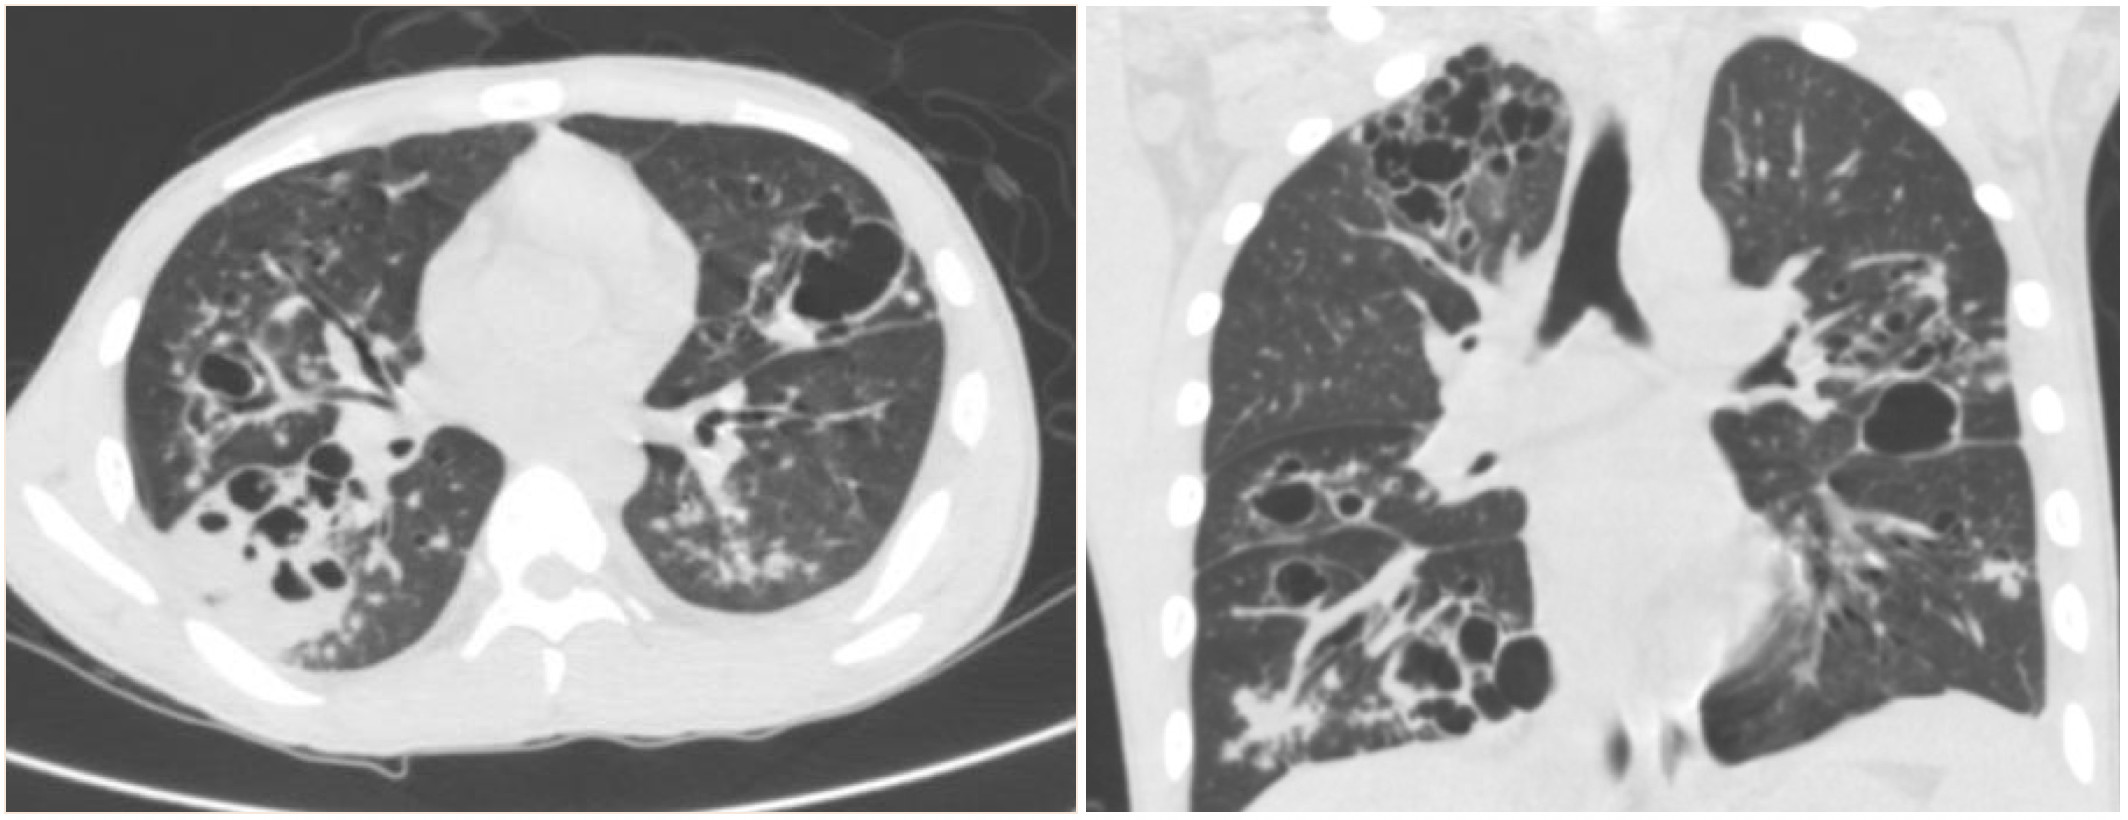

流感病毒相关细菌性肺炎与所谓的社区获得性肺炎的病原菌不同,以金黄色葡萄球、肺炎链球菌和流感嗜血杆菌等最为常见。特别是合并金黄色葡萄球菌感染,是流感病毒肺炎的一个显著的特点。胸片表现为肺部炎性渗出影,病变进展迅速,短期内可形成肺脓肿、肺空洞、脓胸和肺气囊,实变区内见蜂窝样或虫蚀样改变【图5、图6】。血源性金葡菌肺炎常继发于金葡菌败血症,一般为双肺多叶受累,病灶多位于外周。目前认为金葡菌所具有的细菌性蛋白酶可促进流感病毒表面蛋白血凝素的开裂,促进病毒活化和复制,增强其感染性和致病能力。临床表现危重,如果治疗不及时,死亡率高达42%。

图5                                                                                                                图6